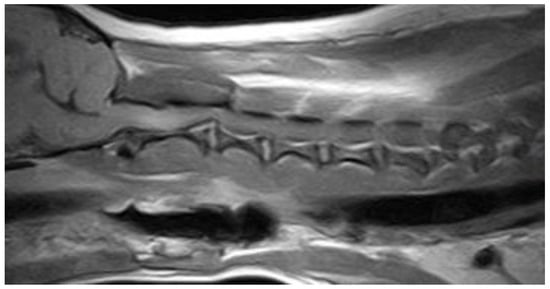

3.2. Diagnostic Imaging